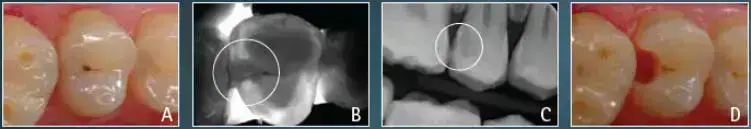

Für eine zuverlässige Kariesfrüherkennung sind bildgebende Verfahren in der Zahnmedizin sehr hilfreich. Gerade Karies in den Zwischenräumen wird mit bloßem Auge häufig erst in einem fortgeschrittenen Stadium sichtbar.

Neben der klassischen Röntgendiagnostik steht uns ein strahlungsfreies Verfahren zur Verfügung. Dabei wird der Zahn mit einem speziellen Licht-/Laserverfahren durchleuchtet. Es entstehen Bilder, die in der Darstellung an Röntgen erinnern, jedoch ohne Röntgenstrahlung auskommen.

Die Zahnstrukturen werden dabei detailliert abgebildet; kariöse Bereiche können als klar abgegrenzte, dunkler erscheinende Areale sichtbar werden. So lassen sich zum Beispiel Approximal- (Zwischenraum-) und Okklusalkaries (Kauflächenkaries) häufig frühzeitig erkennen.